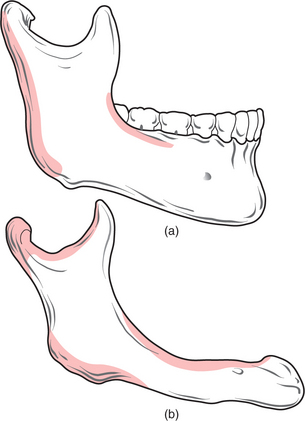

Changes occur in the morphology of the jaws after tooth loss (Fig. 11.1). The jaws are composed of alveolar and basal bone. The alveolar bone and periodontium support the teeth, but neither have a physiological function once the teeth are lost, and are therefore resorbed. Alveolar bone changes shape significantly with tooth loss, in both the horizontal and vertical planes, but the overall pattern of resorption is largely predictable. In the maxilla and in the anterior aspect of the mandible bone loss occurs typically in both the horizontal and vertical planes. In the posterior mandible the bone loss is mostly in the vertical plane.

Fig. 11.1 (a) A dentate mandible, illustrating the extent of supporting (alveolar) bone around the teeth. (b) An edentulous mandible, illustrating the extent of resorption of alveolar bone that occurs following loss of the teeth. Note also that the angle between the ascending ramus and body of the mandible is more obtuse than in (a), and the mental foramen is also closer to the crest of the edentulous ridge. The shaded areas in this illustration indicate areas of resorption of mandibular bone with advancing age.

After physiological resorption has occurred, the remaining jaw structure is termed the ‘residual ridge’. The bone that remains after alveolar bone has resorbed is termed ‘basal bone’. Marked resorption sometimes affects the entire mandible (Fig. 11.2). Basal bone does not change shape significantly unless it is subjected to excessive local forces, for example, in the edentulous anterior maxilla in association with retained natural lower incisors.